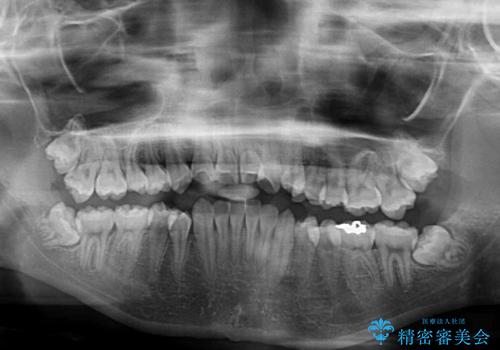

- 下顎の前突感と前歯の叢生を気にして来院された患者様です。

下顎前方位の骨格のため、下顎歯列に対して上顎歯列の幅が狭くなっていました。

急速拡大装置を用いて上顎骨を側方に拡大し、上顎の叢生を解消するとともに下顎歯列拡大により下顎の叢生も解消することとしました。